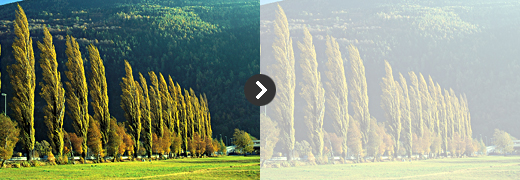

백내장의 증상

백내장의 증상

- 1시아혼탁 및 시력저하

- 안개 낀 것처럼 뿌옇게 보이며 멀리 있는 사물이 불분명하게 보입니다.